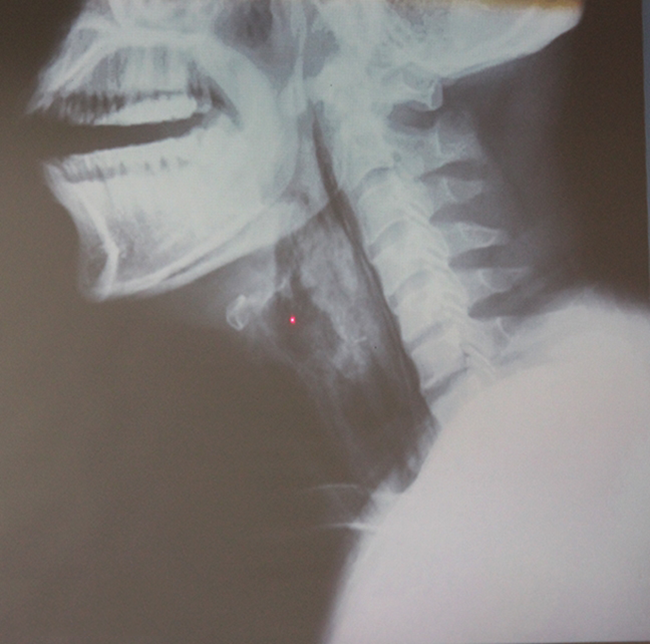

| Cổ họng anh D. bị phù nề và tổn thương nặng vì bệnh viêm thanh thiệt cấp. |

Thạc sĩ, bác sĩ Phạm Quang Tú, Bệnh viện Tai Mũi Họng TP.HCM cho biết: “Anh D. đến bệnh viện khi cơ thể đã tái tím, mạch và huyết áp không đo được. Bệnh nhân ngưng thở, tim suy yếu.

Cổ họng phù nề nặng, chúng tôi vừa cấp cứu vừa phát báo động đỏ để các bác sĩ có thể hỗ trợ ngay. Nếu bệnh nhân vào bệnh viện trễ 10 phút, anh D. sẽ tử vong, mà có cứu được, bệnh nhân cũng chết não và sống đời thực vật”.